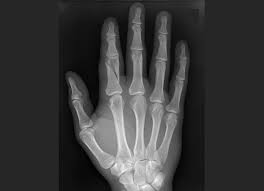

Two spiral fractures sustained following only minor trauma. Complete fractures are categorized based on the way the bone breaks. It occurs due to a rotational, or twisting, force. Try our newest study sets that focus on spiral fracture to increase your studying efficiency and retention. Detailed step by step desription of intramedullary nailing for simple fracture, spiral located in our module intramedullary fixation is valuable and appropriate for the majority of tibial fractures. Other articles where spiral fracture is discussed: A spiral fracture is a bone fracture occurring when torque is applied along the axis of a bone.1 spiral fractures often occur when the body is in motion while one extremity is planted. Spiral fracture femur (there is a significantly displaced spiral fracture of the proximal femoral. A spiral fracture, also known as torsion fracture, is a type of complete fracture. A spiral fracture is a bone fracture caused by a twisting force. A spiral fracture is usually treated right away with surgery. Summary summary (text) medline pmcid list. Know ways to lower your risks in the first place.

Spiral fracture — beware the horns 03:03. A spiral fracture is a bone fracture caused by a twisting force. A fracture, sometimes called a torsion fracture, in which a bone has been twisted apart. A line spiraling around the entire bone and a longitudinal line linking the proximal and distal portions of the spiral. A spiral fracture, characterized by a helical break, commonly results from a twisting injury.